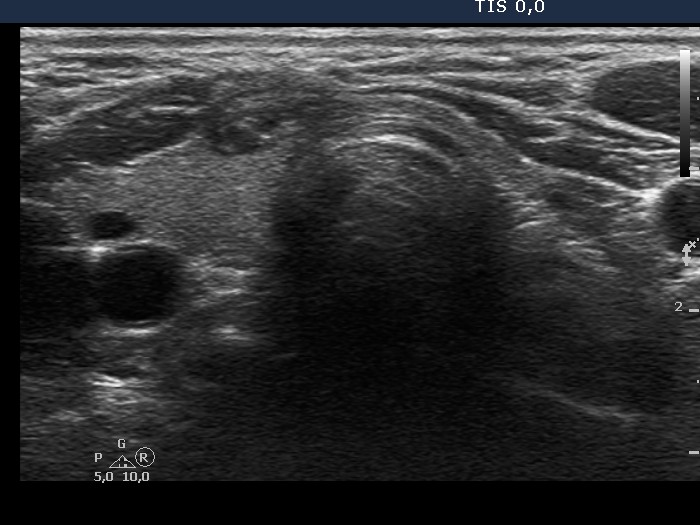

Ultrasonography. There was a mixed solid cystic nodule in the right side of the isthmus. Otherwise, the thyroid was intact.